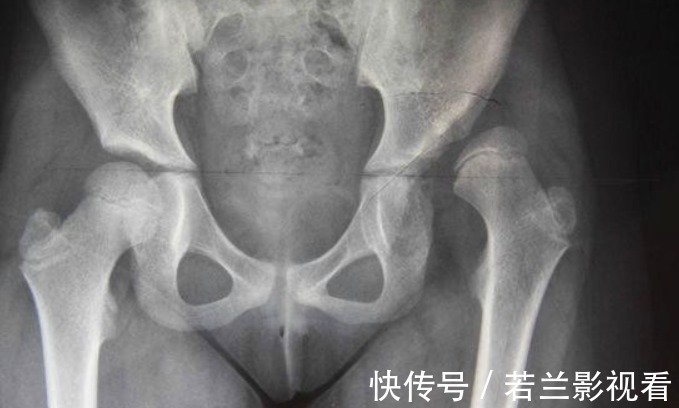

5.患有先天性髋关节脱位这种疾病不容易发现,不痛不痒,只有仔细观察才会发现宝宝屁股两边不对称,双腿不愿意分开,走路时的姿势像鸭子般左摇右摆。先天性髋关节脱位是一种儿童四肢畸形的疾病,主要受遗传因素、子宫内机械性因素及婴儿的包裹方法等多项因素影响。肌肉张力下降,不能顺利爬行。脱位侧的下肢会显得比较短,走起路来一跛一跛的;即使情况最轻的,大腿皮肤纹理也会出现不对称的情况。 通过大动作异常,辨别宝宝疾病宝宝大动作异常可能预示着某种疾病,任何疾病都是早发现治愈可能性高,能减少疾病对宝宝的伤害。